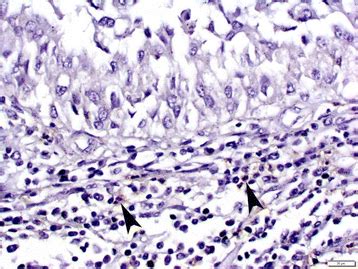

Does "differentiated" mean it looks different? | Pathology ... from i0.wp.com Tumor markers are substances present in the blood when you have cancer. Although an elevated level of a tumor marker may suggest the presence of cancer, this alone is not enough to. Most tumor markers may be present in a healthy individual's body in very low levels. Tumor markers are diagnostic as well as prognostic about a certain type of cancer. As long as a patient's tumor has continued to grow following prior. This marker test is performed by taking a small amount of blood and testing it. Some tumor markers listed below are targets for targeted therapy in multiple cancers but serve as tumor markers for only a subset of cancers. Response to cancer treatment is defined several ways: